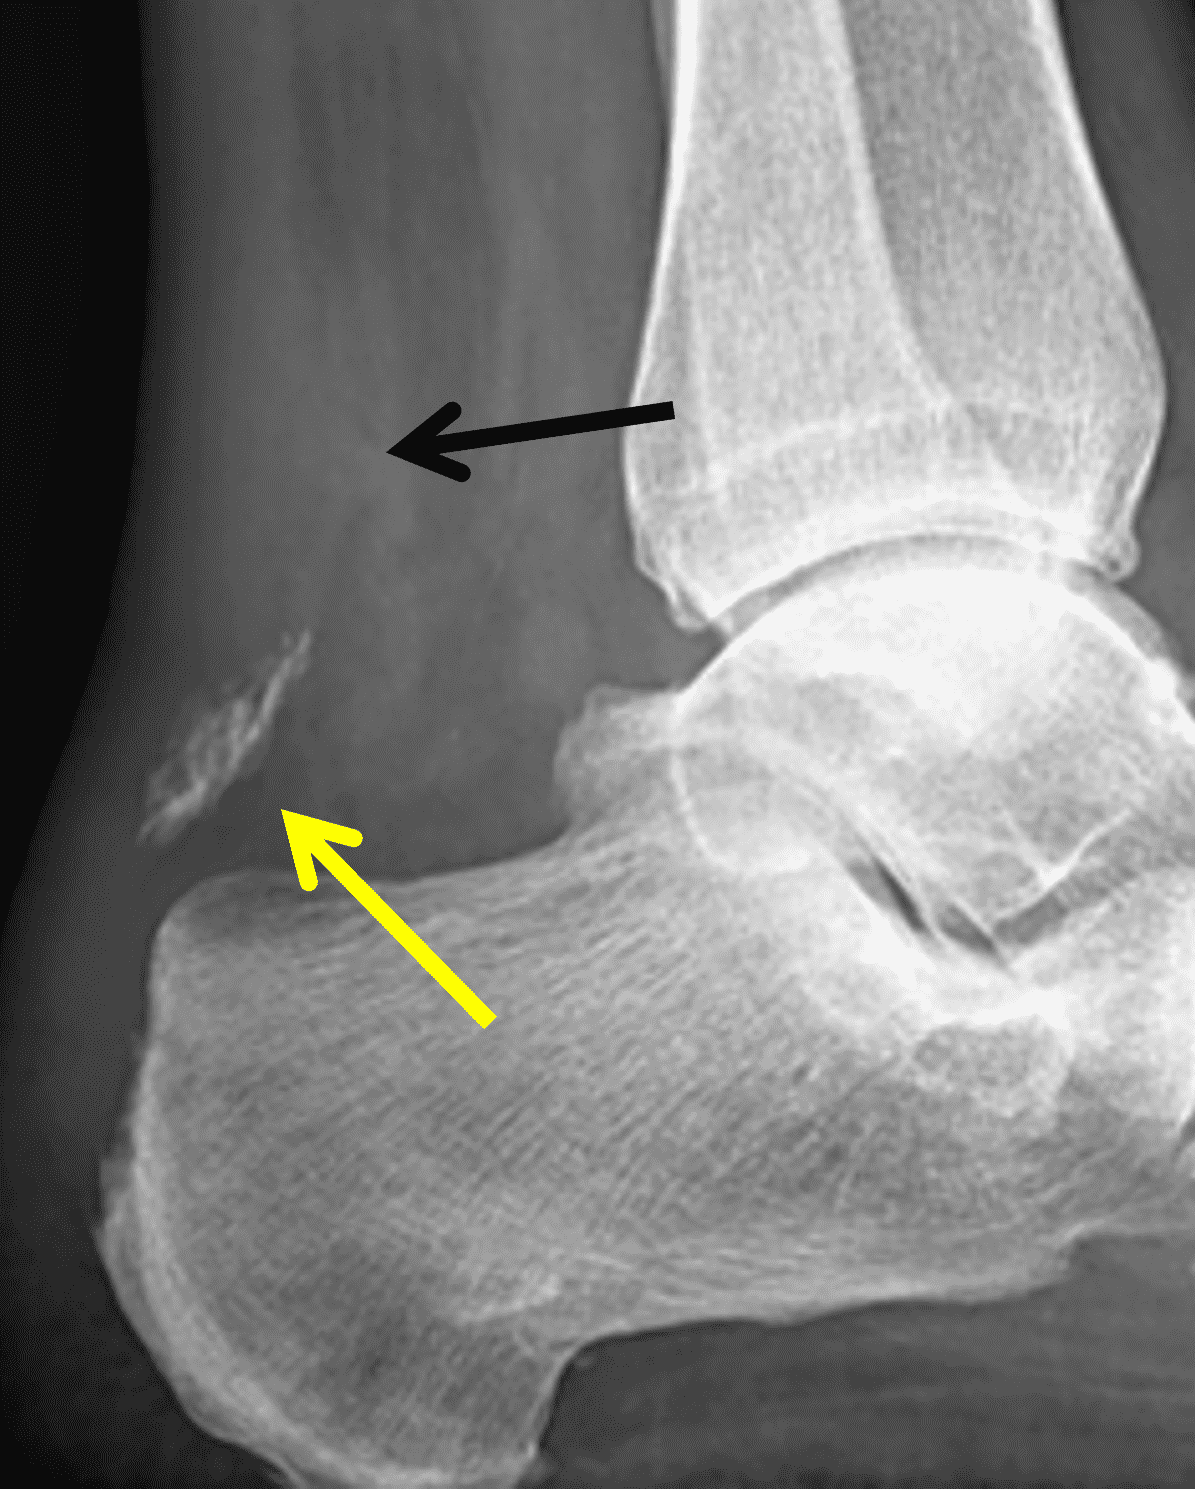

Distal tendon avulsions, with or without an accompanying calcaneal fracture, can also occur after acute trauma (Figure 7). Additionally, spontaneous or low-energy posterior calcaneal avulsions have been reported in patients with longstanding diabetes mellitus and neuropathy.25 Repair techniques for avulsion fractures depend on the fragment size with larger fracture fragments transfixed by cannulated cancellous screw and Kirschner wires to varying success. Smaller bone fragments are debrided with reinsertion of the tendon to the remaining calcaneus.26,27

Figure 7: Distal Achilles tendon avulsion fracture in a 56 year-old man who stepped off his deck and felt a “pop” in his ankle with subsequent pain and swelling. (5A) Lateral radiograph demonstrates a retracted and rotated fracture fragment of the posterosuperior calcaneus (yellow arrow). Note the soft tissue swelling and indistinct contour of the Achilles tendon (black arrow). (5B) Sagittal fat-suppressed, T2-weighted image shows no tendinosis of the Achilles (arrowheads), soft tissue edema surrounding the fracture fragment (arrow), and marrow edema in the posterior calcaneus (asterisk). (7C) Sagittal T1-weighted image shows the retracted fracture fragment, rotated 180°, with cortical bone along the anterior aspect of the fragment (arrow).